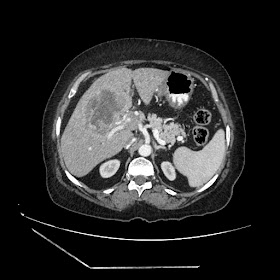

A 70 years old woman with Obstractive jaundice & palpable GB

Latest Radiological images: